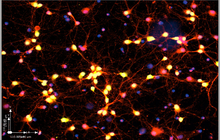

- General and specialized tissue and cell staining

- Immunocytochemistry (ICC) technique

- Immunohistochemistry (IHC) technique

- Perform tunnel technique to evaluate apoptosis

On the other hand, in cutting-edge sciences such as tissue engineering, the use of up-to-date techniques for section preparation and cell tracking and engineered tissue structure has contributed significantly to the development of new studies.